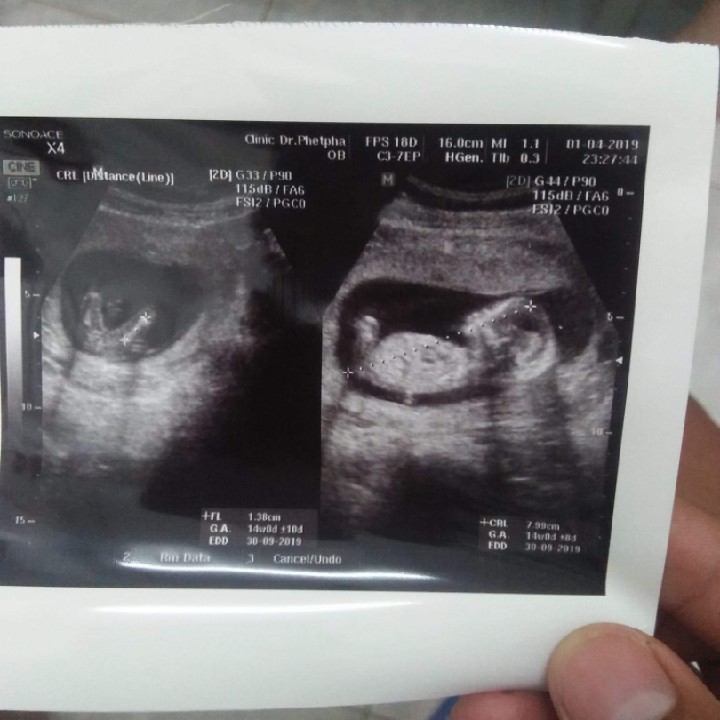

13w ค่ะ

14w จ้า ชัดมาก